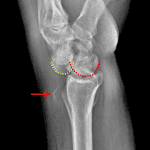

- Acute perilunate dislocation

- Acute scaphoid waist fracture with 5 mm radial displacement of the distal fracture fragment

- Remote healed distal radial fracture and nonunited ulnar styloid tip fracture

- Perilunate dislocation

Acute transscaphoid perilunate dislocation with 5 mm radial displacement of the distal scaphoid waist fracture fragment.

Remote healed distal radial fracture and nonunited ulnar styloid tip fracture.